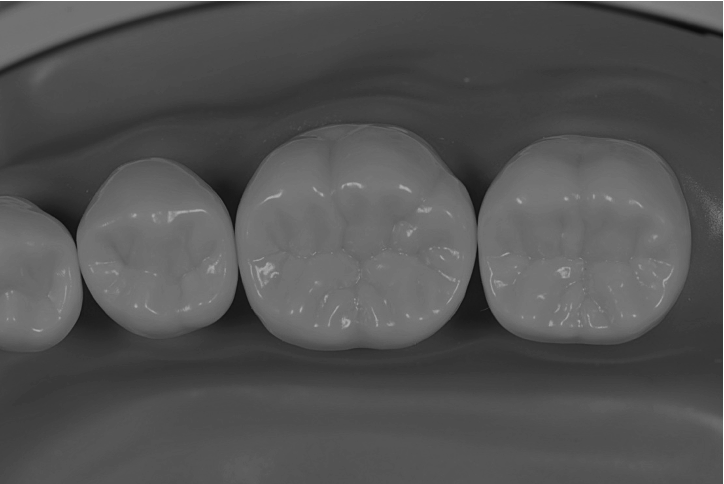

症例(患者様から掲載の許可を得ています。)

左上の奥歯の銀歯を白くしたいことを主訴に来院されました。

一見何もないように見えますが、、、

歯と銀の詰め物の間には黒い汚れが入ってきています。

この方の場合は銀の詰め物にしてから1年ほどしか経っていないとのことでしたが、

これがあと5年放置されていたらと考えると恐ろしいですね。

修復物の適合はこういうところに如実に現れてきます。

綺麗に汚れと虫歯をとった後に、ラバーダムを装着した様子です。

歯が完全にお口の中で隔離されているのがわかりますね!

ダイレクトボンディングで充填した後になります。

段差もなく綺麗に詰まっていますね!✨

Before

After